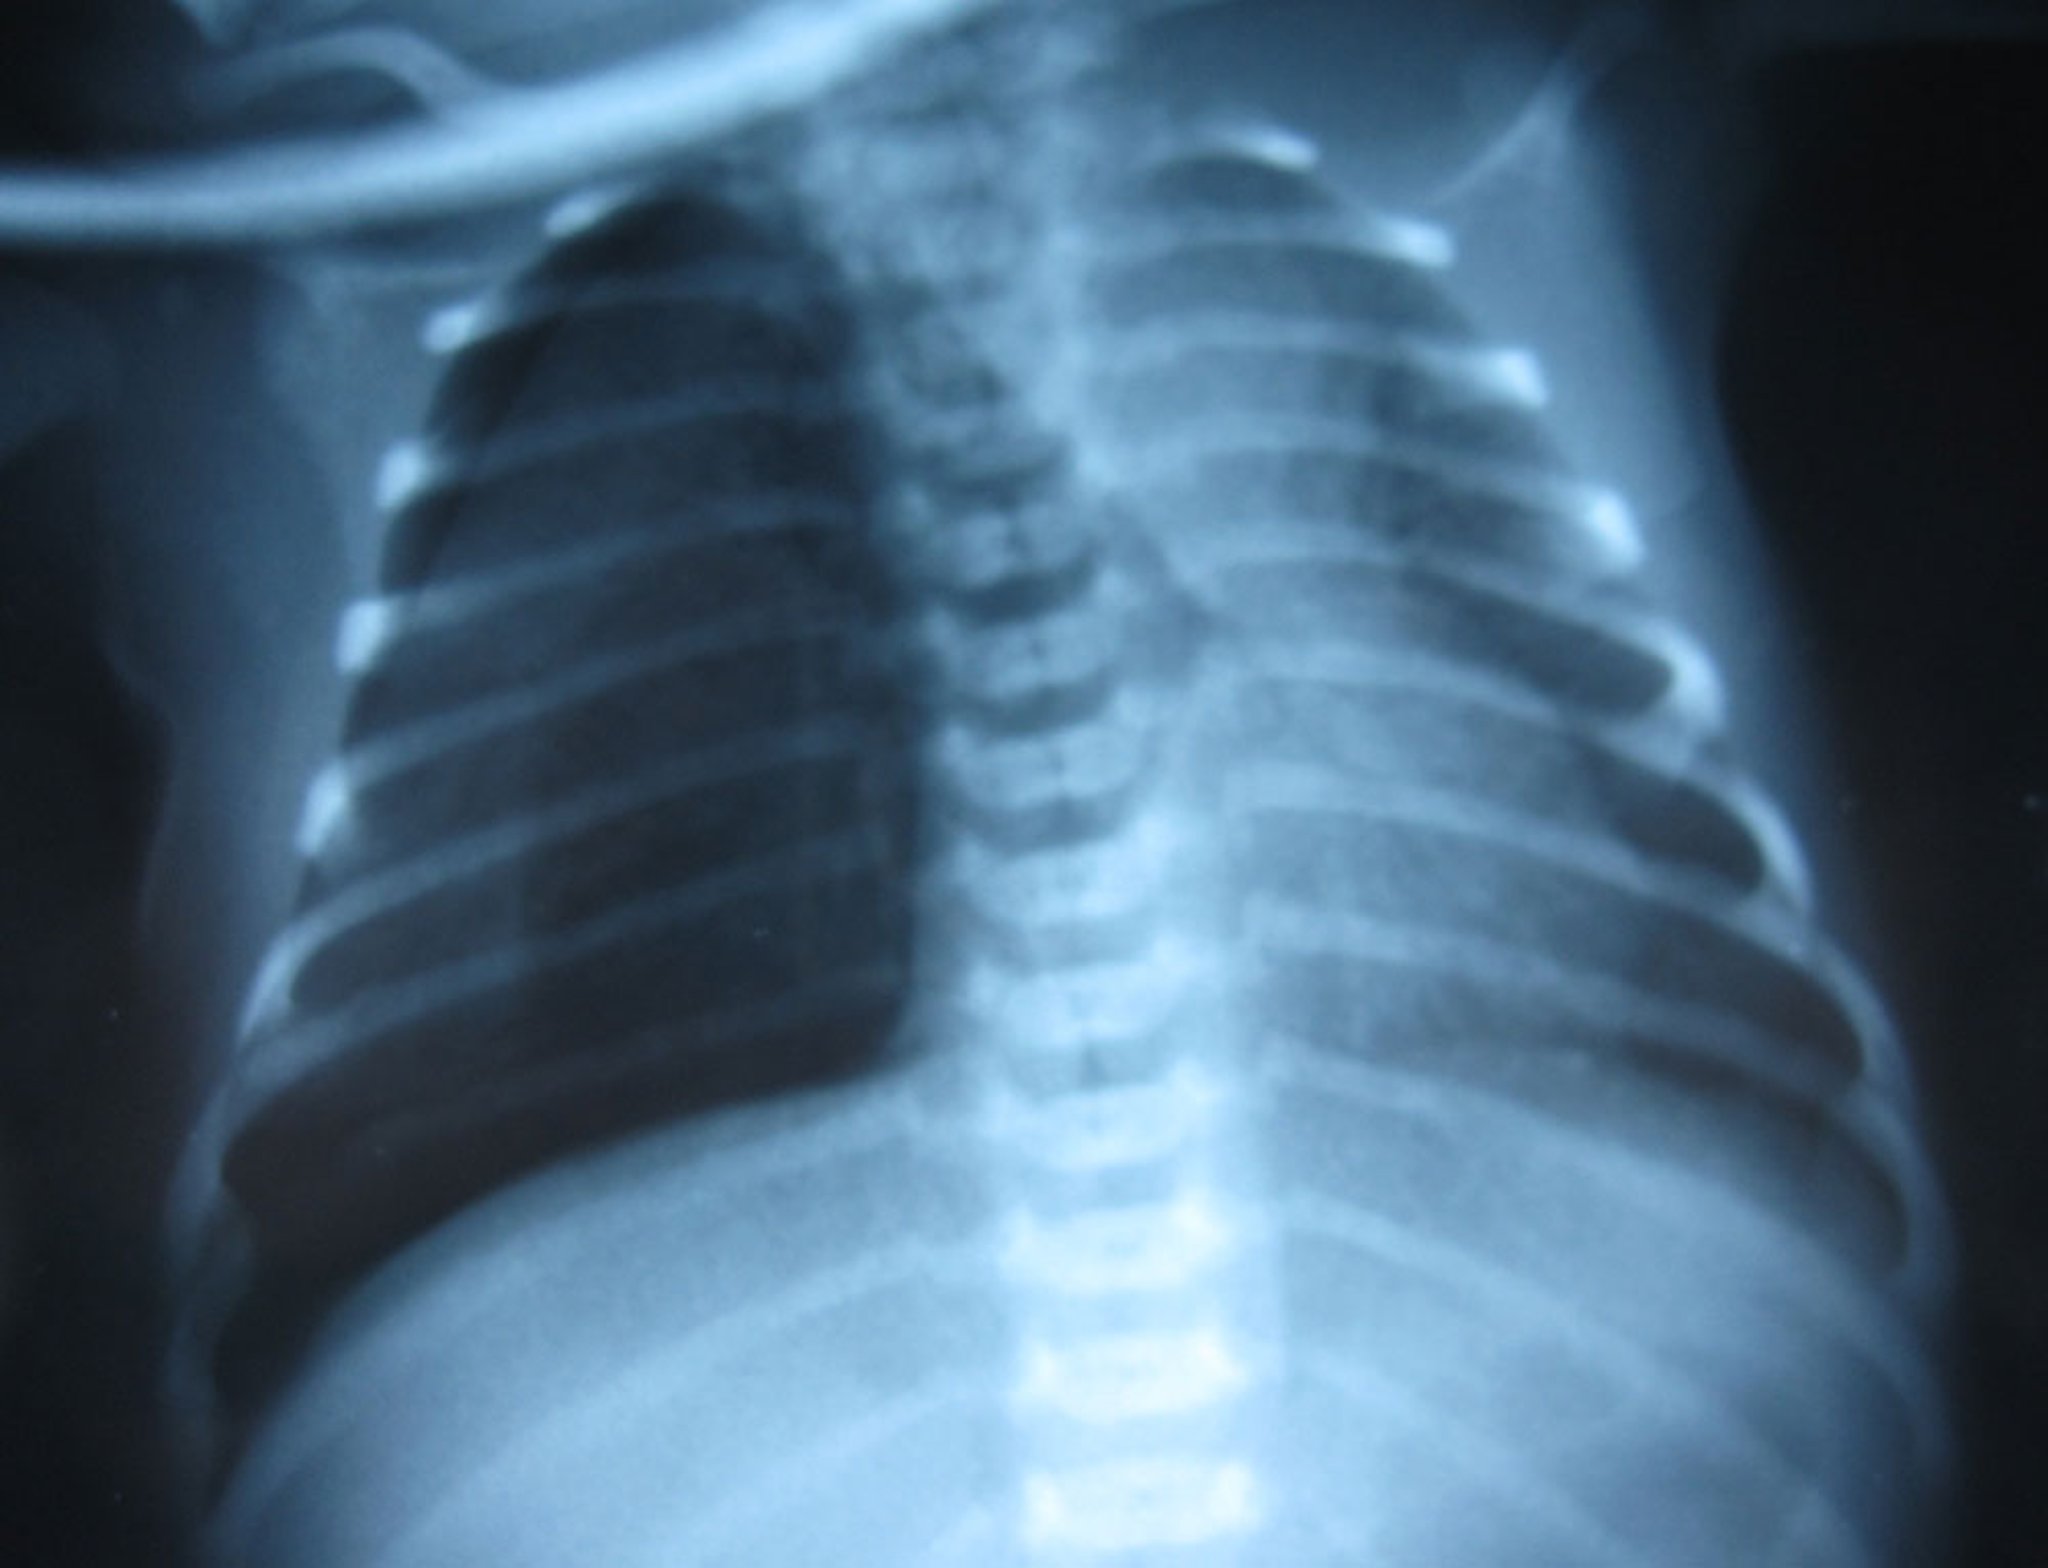

After placement of a pigtail chest tube, the right lung in this image has re-expanded, with lung markings clearly visible.

The pulmonary edema is due to congenital heart disease (total anomalous pulmonary venous return) and is not directly related to the pneumothorax.

Image courtesy of Arcangela Balest, MD.